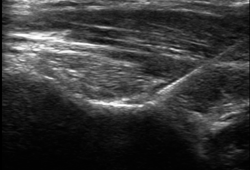

Tijdens de procedure

De behandeling gebeurt onder beeldgeleiding (röntgendoorlichting of echografie). U ligt op de buik, rug of zij, afhankelijk van de plaats van infiltratie. Via het infuus kan je een licht verdovend middel krijgen. De huid wordt ontsmet en lokaal verdoofd, waarna de arts de naald positioneert. Vervolgens wordt het medicijnmengsel ingespoten.